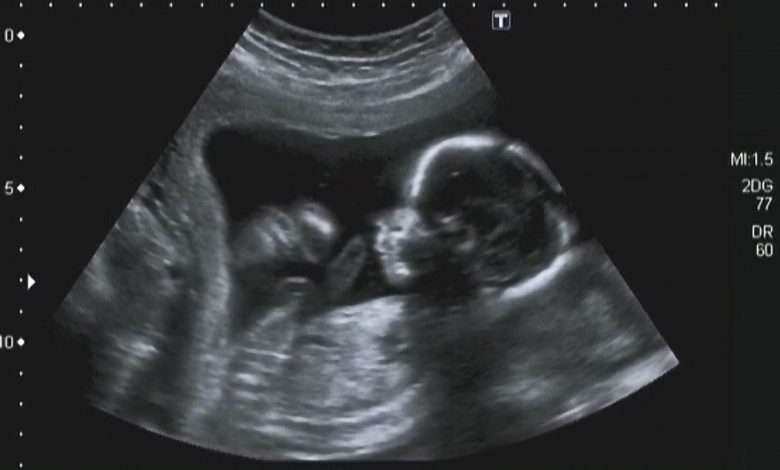

An unplanned pregnancy

Not every woman smiles and is happy when they do a pregnancy test and discover that there is a bun in the oven. A positive pregnancy test leaves some women reeling, blindsided, shocked and frankly, not at all happy to find out that despite their best intentions and precautions, they’re having an unplanned pregnancy.